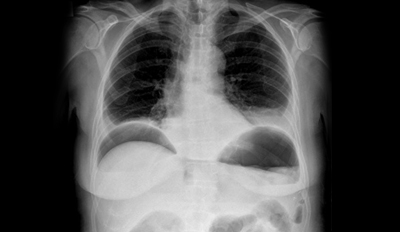

Subdiaphragmatic Abscess: Complication of Emergency Laparotomy